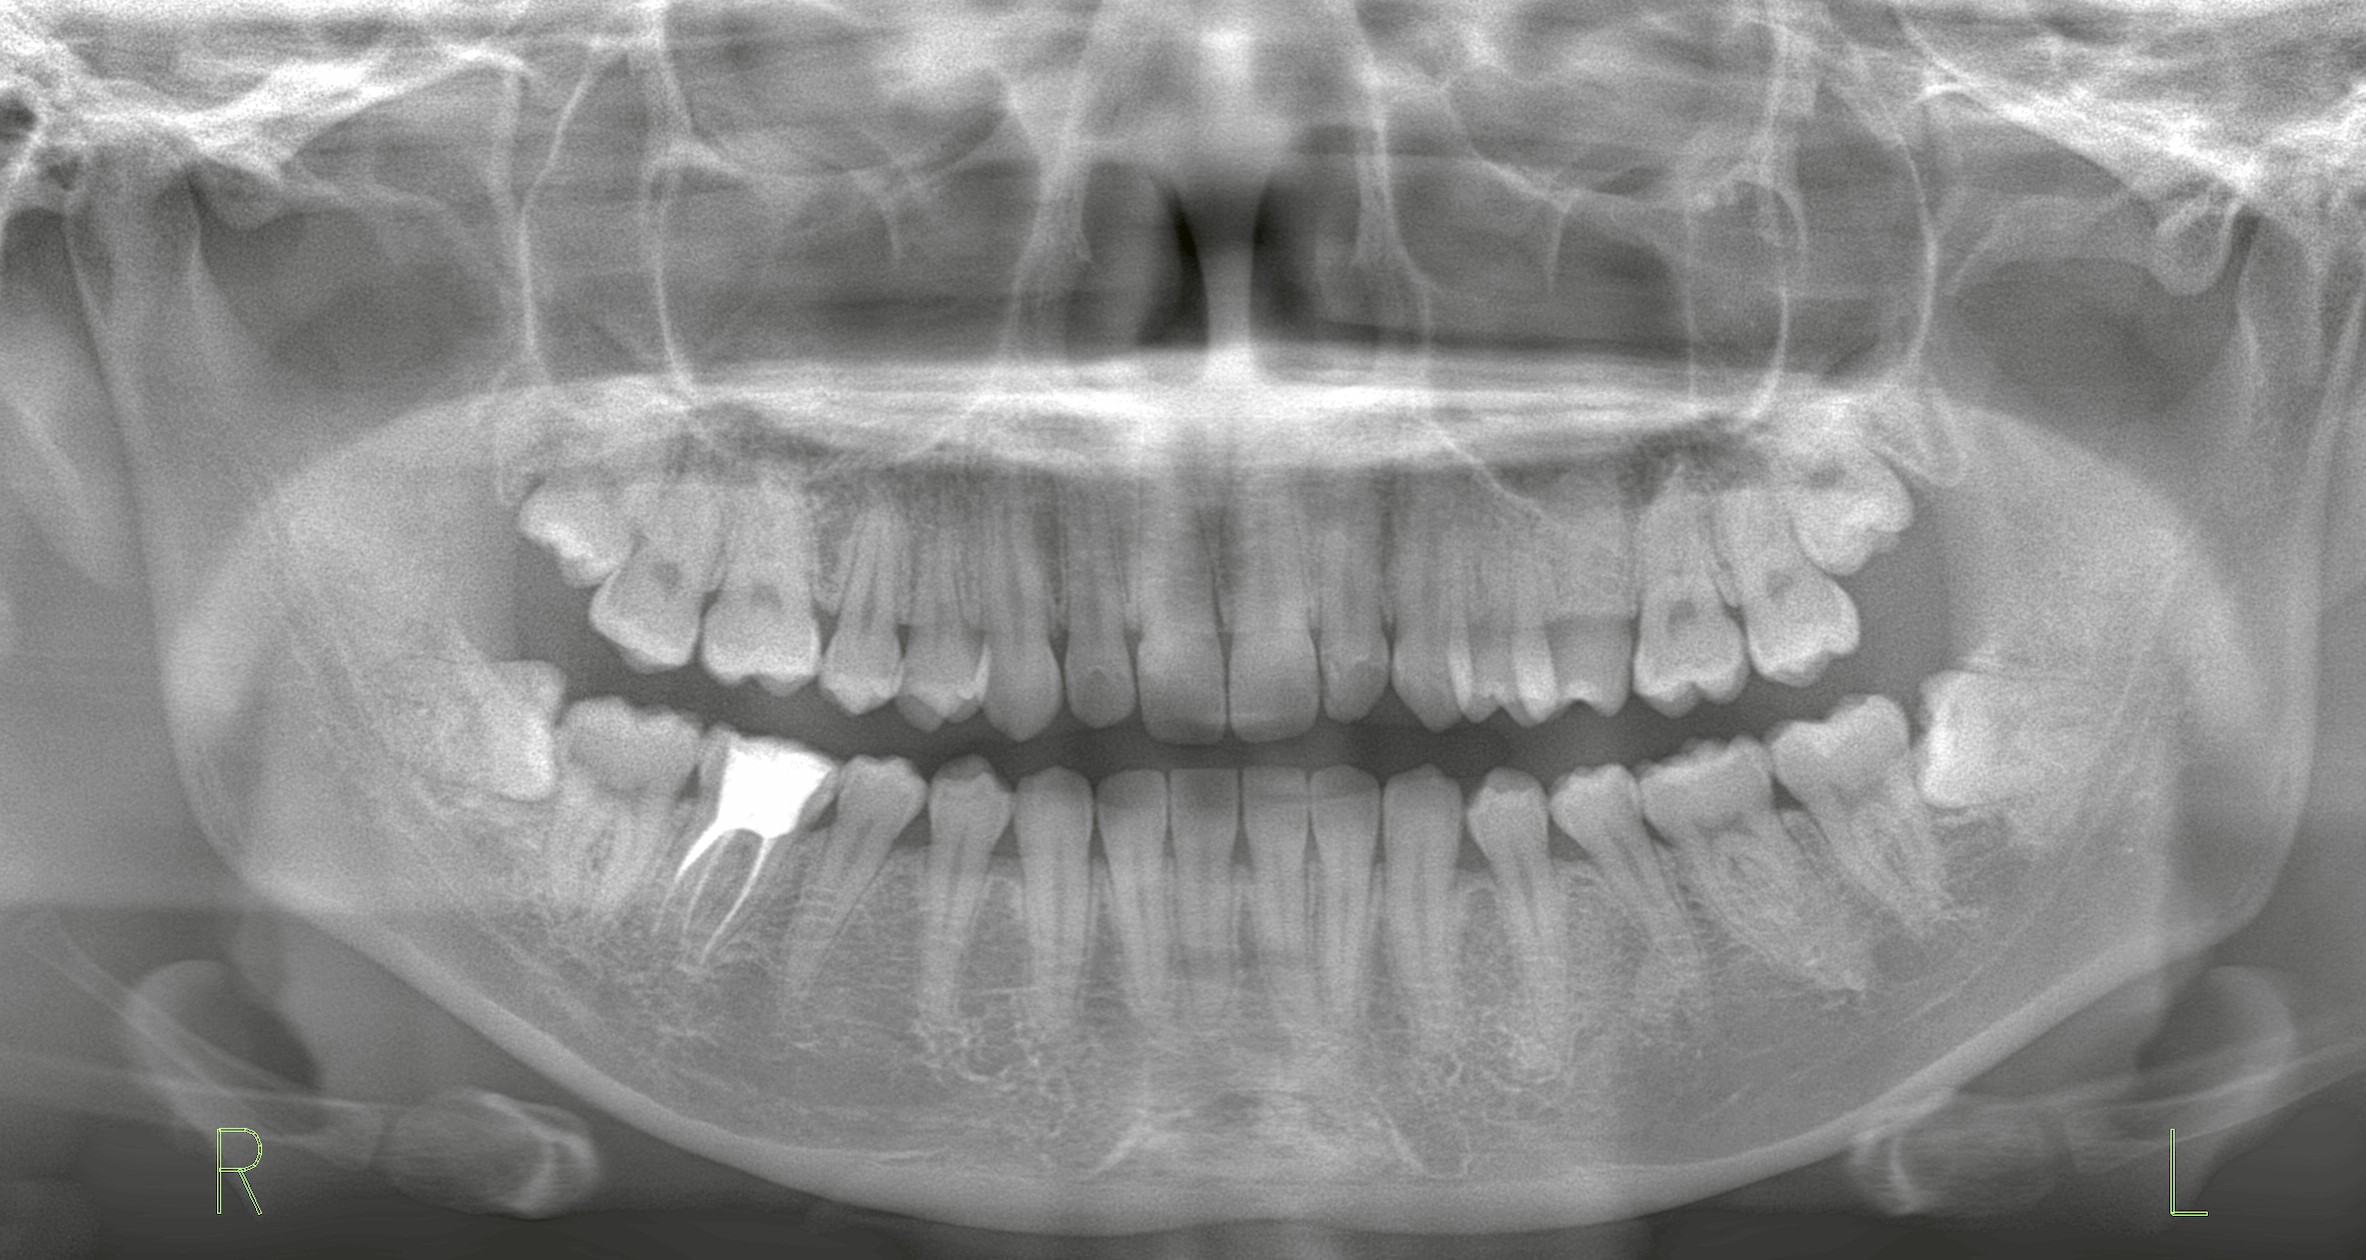

右上下の親知らずを一度に抜歯したケース

「右下の奥が腫れて痛む」とのことで来院された患者様。

診察とレントゲン検査の結果、右下には水平埋伏智歯(横向きに埋まった親知らず)があり、炎症を起こしていました。

右下の抜歯は必須でしたが、同時に右上にも埋伏歯があることが判明。

右上の親知らずは完全には萌出しておらず、もしこのまま出てくるなら炎症や虫歯のリスクがあるため、患者様と相談し上下同時抜歯を行う方針にしました。